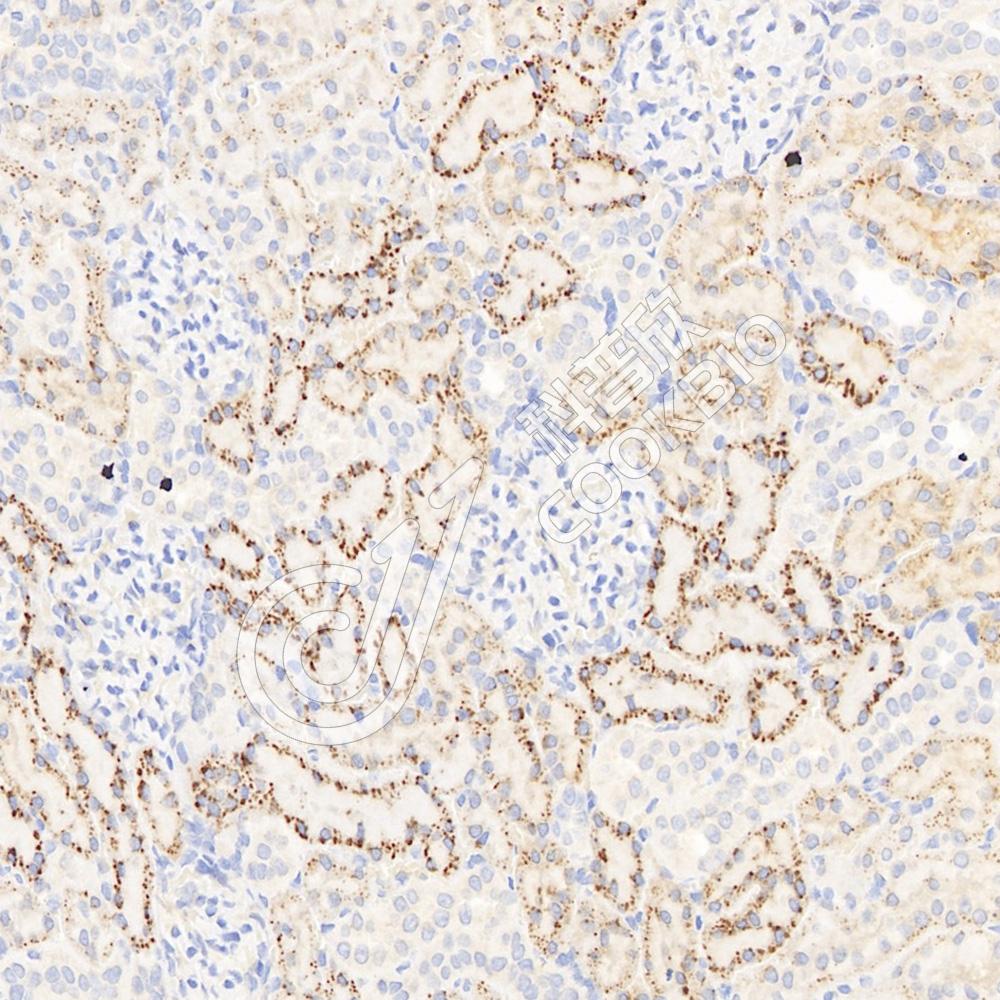

IHC检测Legumain蛋白(货号 K1335340).

样品: 小鼠肾, 4%多聚甲醛 (货号KSG1101) 固定12-24小时.

抗原修复: 柠檬酸抗原修复液(干粉, pH 6.0) (KSG1201), 98℃, 20分钟.

—抗: 1: 400稀释, 4℃ 孵育过夜.

二抗: S-vision免疫组化多聚二抗(山羊抗兔),即用型 (货号KB3906), 室温孵育20分钟.

样品: 大鼠肾, 4%多聚甲醛 (货号KSG1101) 固定12-24小时.